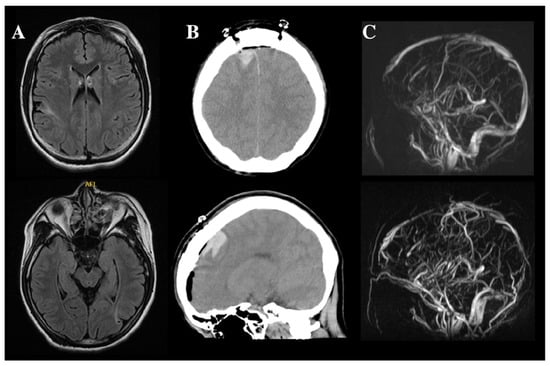

2.1. Cerebral Hemorrhage and CVST